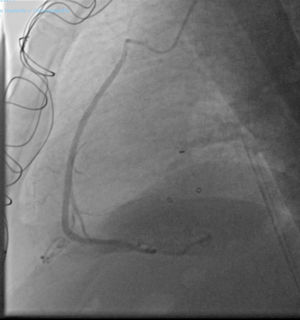

Post-surgery recovery was favorable. Since discharge the patient is in functional grade I (NYHA scale). A year after the surgery a coronary angiogram showed that the SVG was patent (Fig. 3).